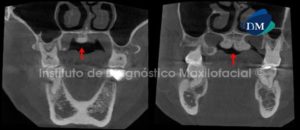

Paciente de sexo masculino de 54 años es referido al Instituto de Diagnóstico Maxilofacial para evaluación del seno maxilar del lado derecho y evaluación de puente protésico en dicha zona.